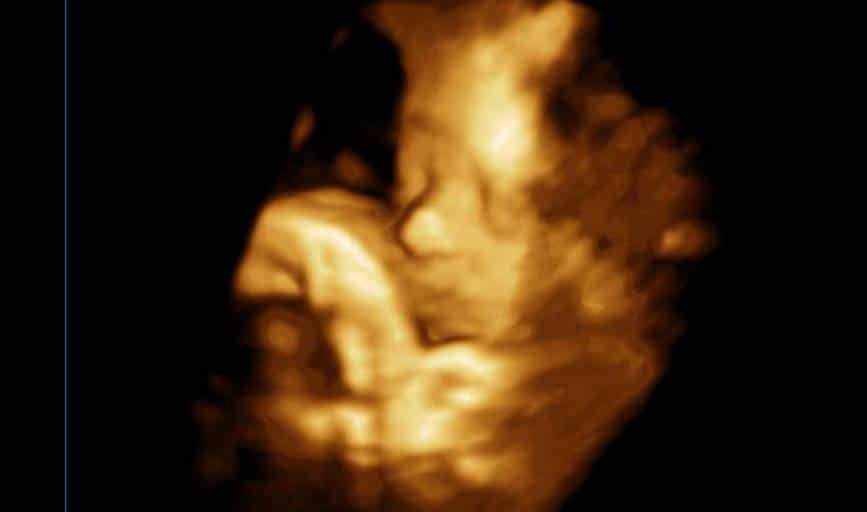

Though optional for any of our ultrasound packages, most parents elect to have a gender determination out of uncontrollable curiosity about their pending baby. A gender sonogram allows us to see if the baby is male or female and will allow parents to start planning for the baby's arrival. The parents may not be the only ones who want to know--perhaps grandparents, friends, co-workers, and other loved ones want to know as well! This elective sonogram can be added to any of the main ultrasound services, so contact us today to find out if your little bundle of joy is a boy or girl!